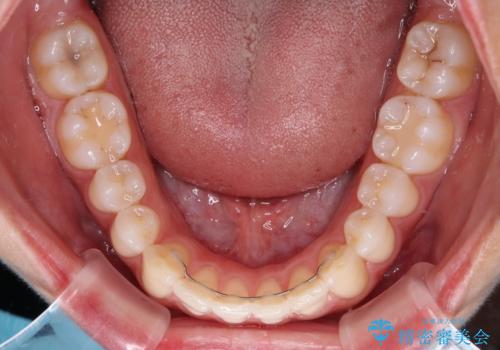

前歯の重なりをインビザライン・モデレートで矯正治療

- 上下前歯の重なりを気にして来院された患者様です。

安価なインビザラインパッケージを用いての治療を希望されており、デコボコの程度が中等度であったため、インビザライン・モデレートを用いて矯正治療を行うこととしました。